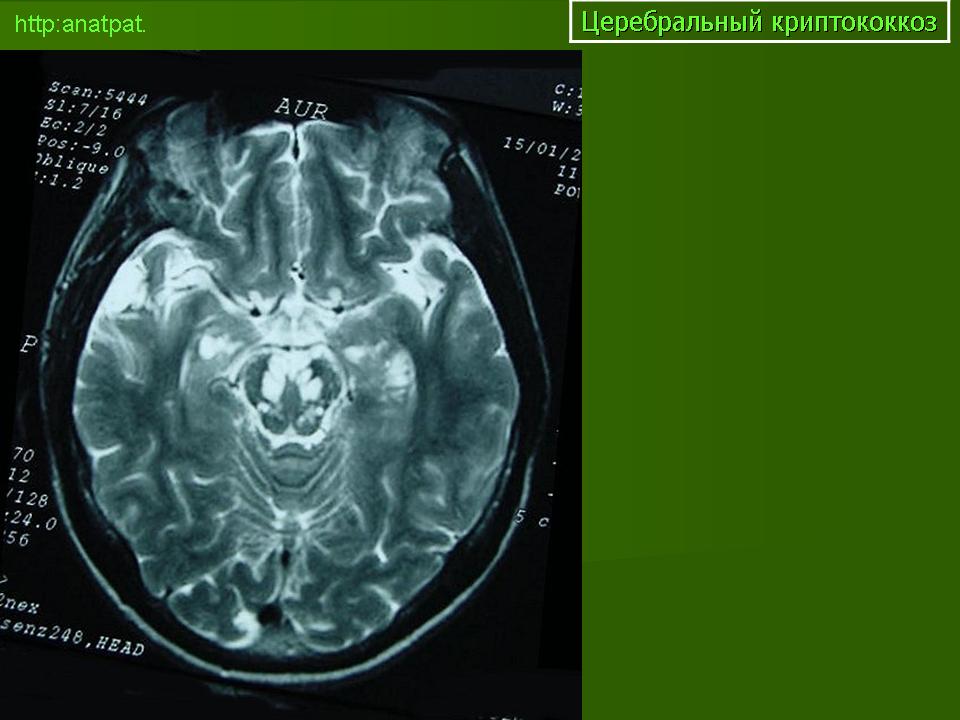

ГМ. Церебральный криптококкоз. +

Церебральный криптококкоз.

Церебральный криптококкоз у ВИЧ инфицированного